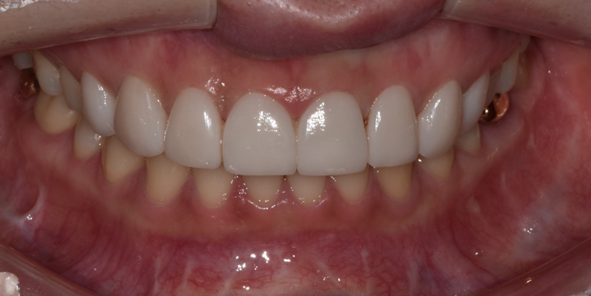

29세 여성

라미네이트 시술

(전) 2022-08-04 (후) 2022-08-12

치아 모양과 색상을 개선하고자 라미네이트 시술을 원하셨던 환자분입니다.

앞니 끝부분이 살짝 파절되셨고, 레진으로 떼워놓은 부분도 있어서 이를 제거하고 다듬은 후 라미네이트 시술을 진행했습니다.

라미네이트 완료 후 치아 모양과 라인이 전보다 고르게 개선된 것을 확인하실 수 있습니다.